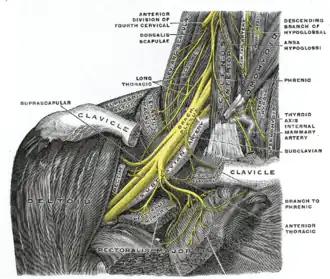

| The right brachial plexus with its short branches, viewed from in front | |

A brachial plexus injury (BPI), also known as brachial plexus lesion[1], is an injury to the brachial plexus, the network of nerves that conducts signals from the spinal cord to the shoulder, arm and hand. These nerves originate in the fifth, sixth, seventh and eighth cervical (C5–C8), and first thoracic (T1) spinal nerves, and innervate the muscles and skin of the chest, shoulder, arm and hand.[2][3][4]

Axillary, Median, Musculocutaneous, Radial, Ulnar.

The brachial plexus is made up of spinal nerves that are part of the peripheral nervous system. It includes sensory and motor nerves that innervate the upper limbs. The brachial plexus includes the last four cervical nerves (C5-C8) and the 1st thoracic nerve (T1). Each of those nerves splits into smaller trunks, divisions, and cords. The lateral cord includes the musculocutaneous nerve and lateral branch of the median nerve. The medial cord includes the medial branch of the median nerve and the ulnar nerve. The posterior cord includes the axillary nerve and radial nerve.[21]